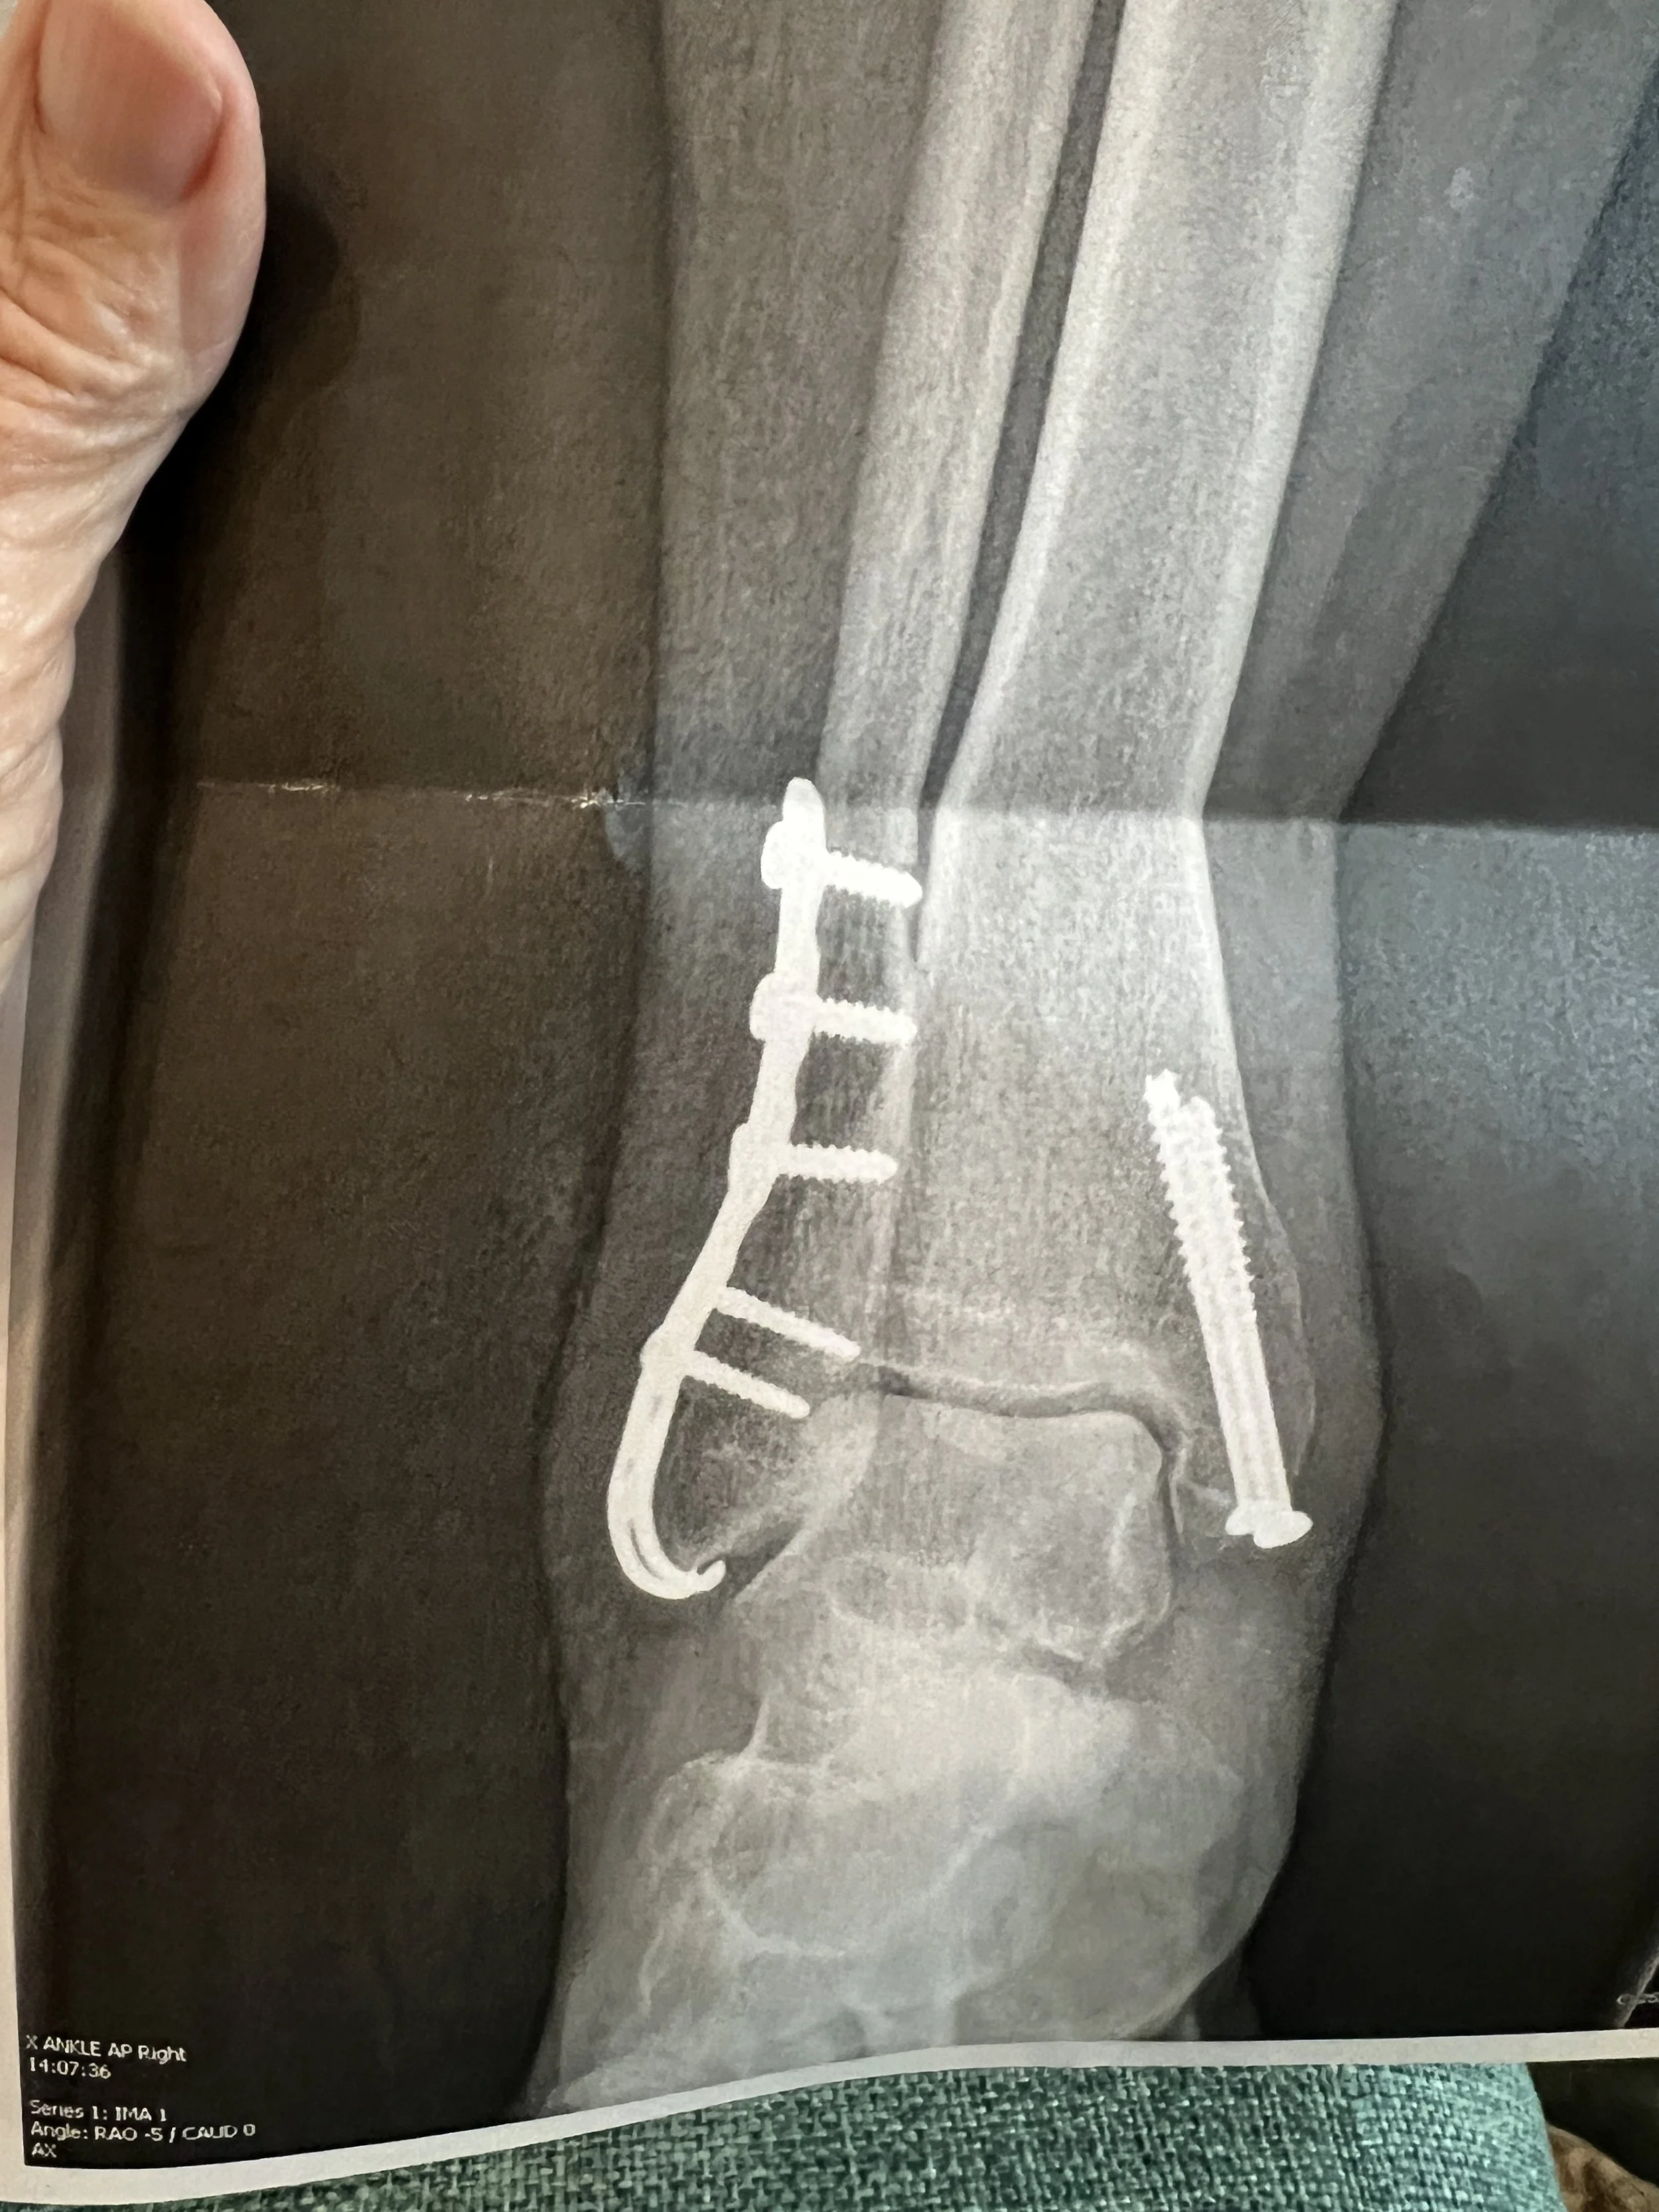

image of legs, a cast and a walker, from someone seated